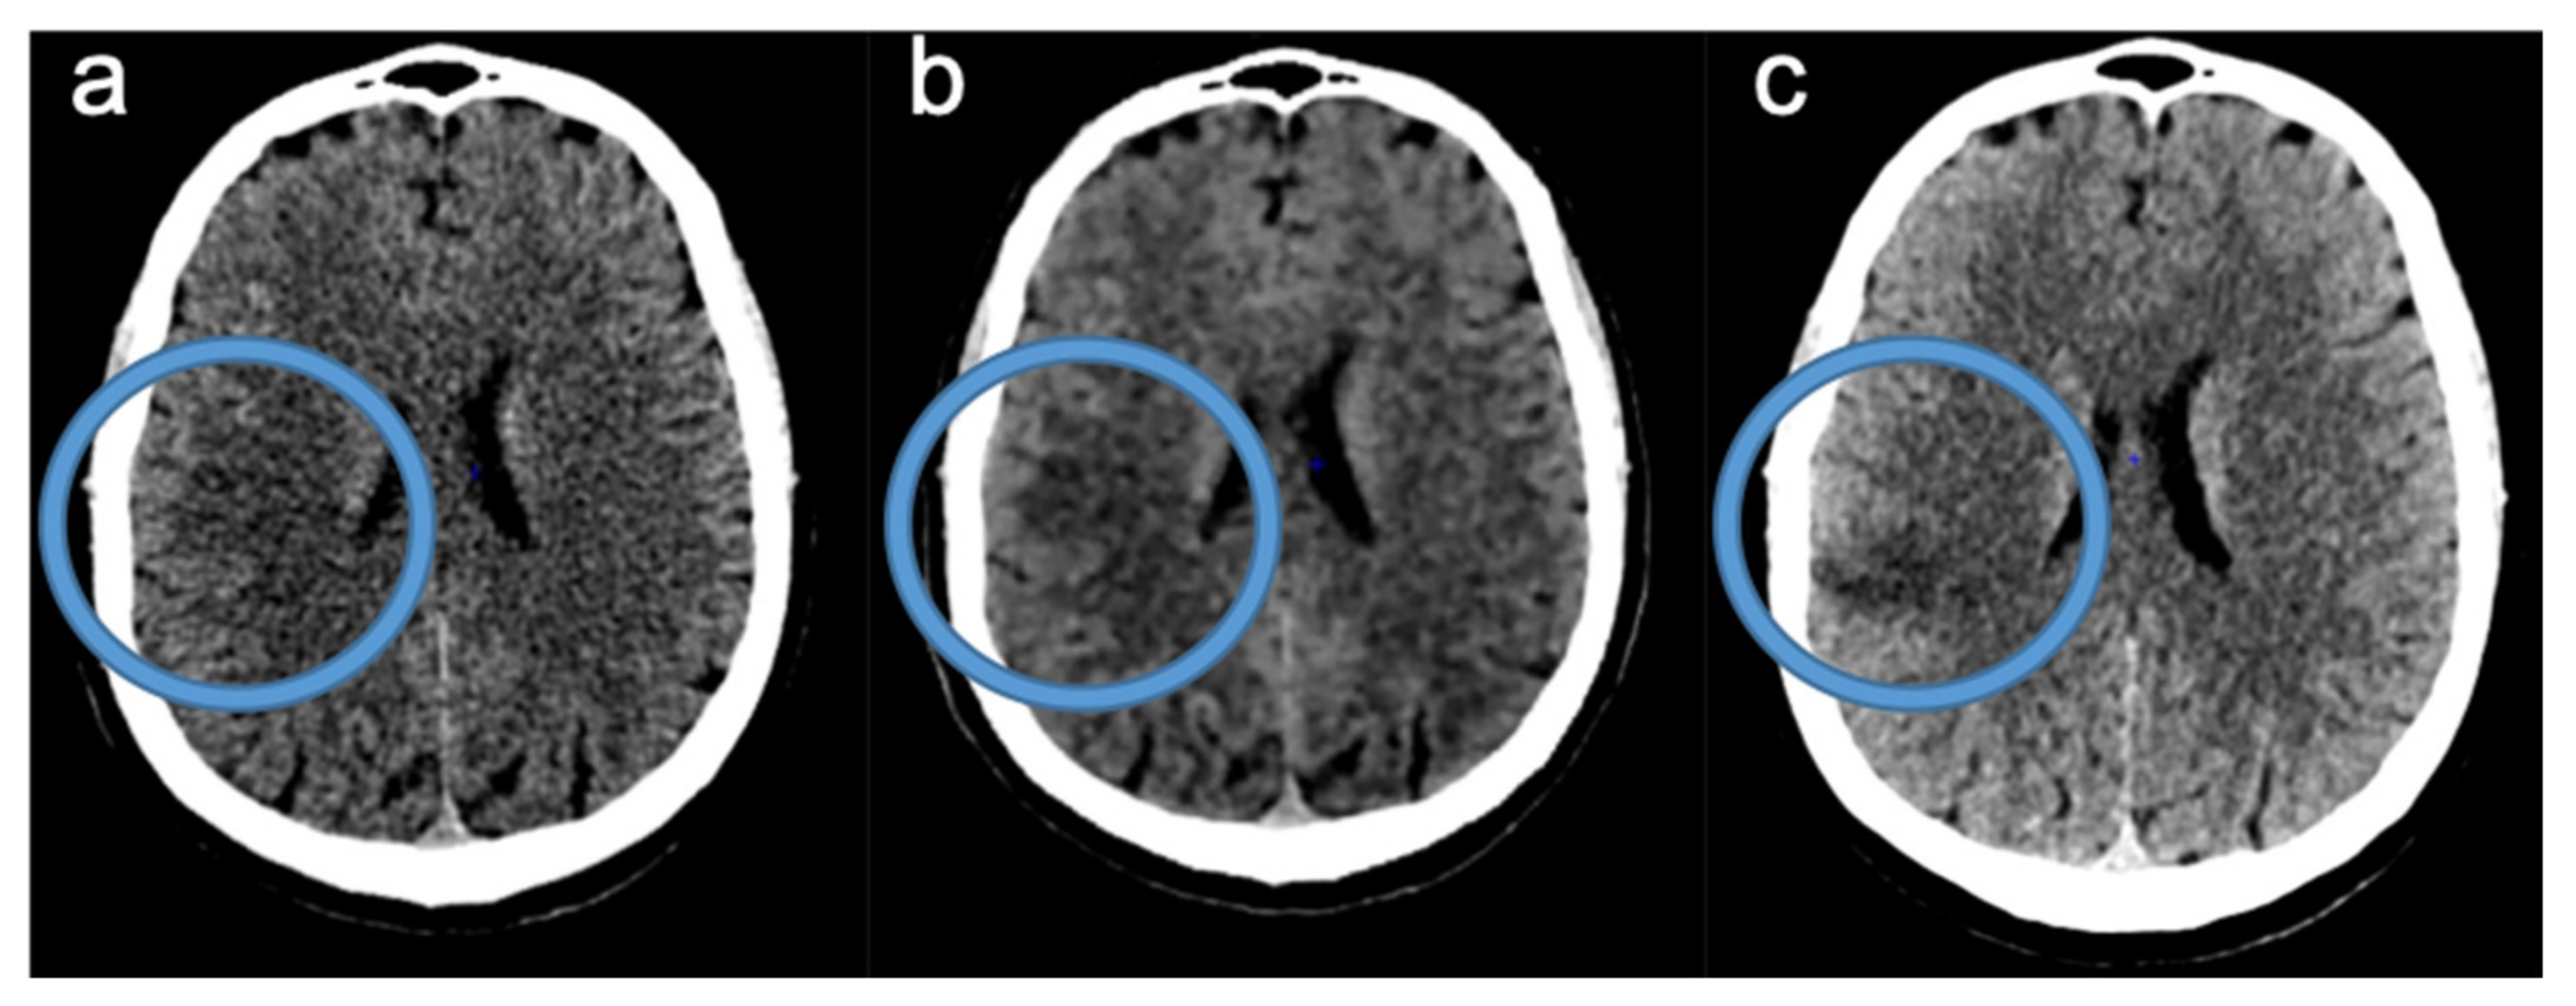

2.2. Image Acquisition and Reconstruction

2.3. Readings of FIRST-LCD and AIDR3D ASPECTS on Baseline NCCT

2.4. Consensus Readings of Final and rCBV ASPECTS